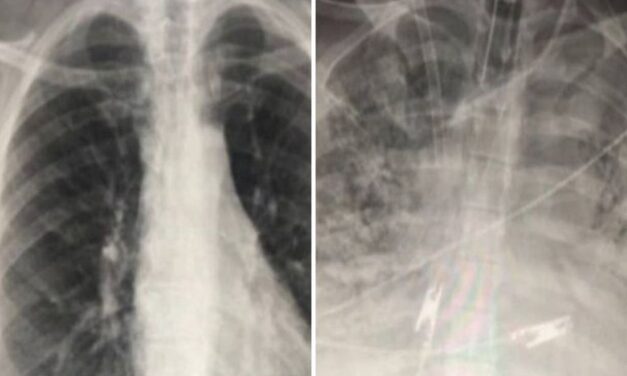

Ebben elsők vagyunk: Nálunk halnak meg a legtöbben rákban

Szerbia évek óta élmezőnyben van a rákos megbetegedések és a halálozás tekintetében Európában, és...